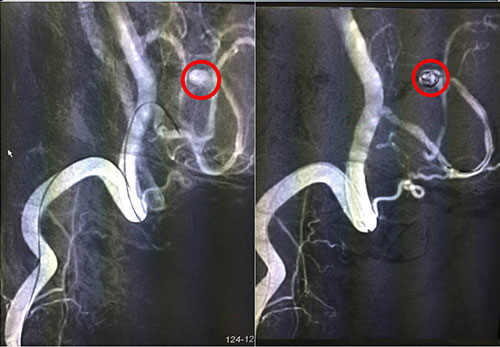

红圈内为术中介入微导管微弹簧

脑动脉瘤的介入治疗,最常用的是用弹簧圈栓塞动脉瘤。简单地说,就是从大腿根部的股动脉插管,将一根很细的微导管通过动脉官腔内直接插到脑动脉瘤内,再通过这根很细的微导管送入一段一段盘旋的微弹簧圈,逐步将动脉瘤腔内填满,诱发血栓形成后,使动脉瘤腔没有血流通过,而正常的脑动脉保留通畅,从而达到治疗的目的。12月6日手术进行,术程顺利,患者安返ICU进行术后监护。

我院神经外科专家潘仁龙等多次与沪上知名神经外科专家联合会诊,讨论患者病情及治疗方案,认为目前诊断明确,患者病情患者具备手术指征,手术方式有:开颅动脉瘤夹闭术和动脉瘤介入栓塞术。由于患者左脑后下动脉瘤体在血管远端,接近脑干边上,手术难度较大,风险极大,在术中、术后均可能发生出血而导致死亡可能。考虑到患者情况高危,又开颅动脉瘤夹闭术相较于介入栓塞术创伤大,风险大,经征求家属意见后,决定为患者全麻下实施左小脑后下动脉瘤介入栓塞术,由我院神经外科专家潘仁龙主任主刀,并特邀华山医院专家协同技术指导。